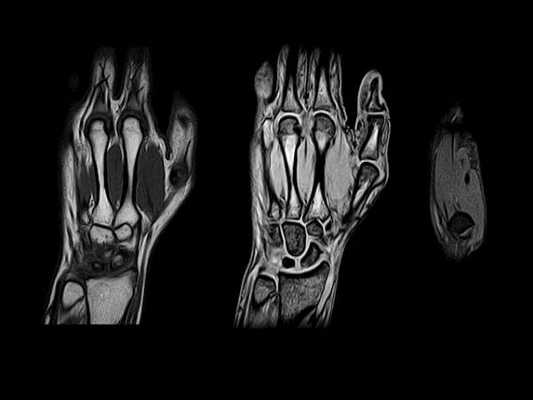

МРТ при переломе запястья

Травмы лучезапястного сустава и кисти - самая распространенная причина проведения МРТ кисти. При лечении перелома в ходе хирургического вмешательства требуется точная репозиция отломков, сшивание сухожилий, нервов. Изучают состояние лучезапястного сустава на МРТ, запястья, пястных костей и пальцев, окружающих их тканей.

После переодевания обследуемый ложится на выдвижной стол. Руку укладывают в нужном положении. Предупреждают, чтобы человек не двигался во время обследования. Внутри цилиндрической части аппарата проходит само обследование. Магнитное поле вызывает реакцию атомов водорода внутри клеток. У всех тканей она отличается из-за разной структуры и содержания воды. В результате сканирования врач получает изображение срезов руки на компьютере, может получить объемную модель кисти.